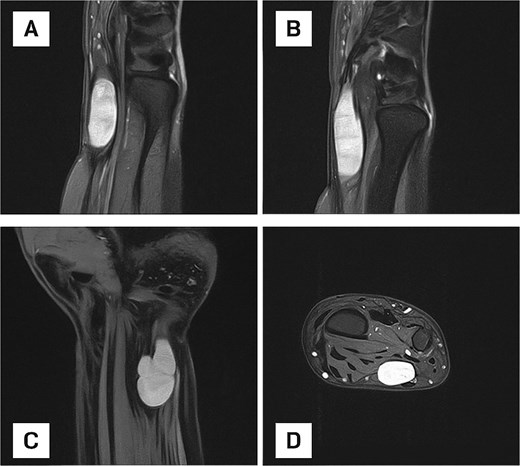

MRI was performed to further characterize the lesion. It revealed a well-defined, oval-shaped, hyperintense mass on the ulnar aspect of the distal forearm, adjacent to the ulna (Fig. 2). The lesion appeared encapsulated, suggesting a cystic or soft tissue origin. Coronal sequences demonstrated a lobulated morphology, raising suspicion for a nerve sheath tumour. No bone involvement or edema was seen.

(A) Sagittal MRI scan of the distal forearm demonstrating a well-defined, hyperintense lesion on the ulnar aspect, suggestive of a fluid-rich or soft tissue mass. (B) Sagittal MRI scan depicting an elongated, well-circumscribed hyperintense lesion with no evidence of bone involvement or perilesional edema. (C) Coronal MRI scan showing a lobulated mass, raising suspicion for a nerve sheath tumour or multilobulated ganglion cyst. (D) Axial MRI view confirming an encapsulated lesion within the deep soft tissue of the distal forearm.